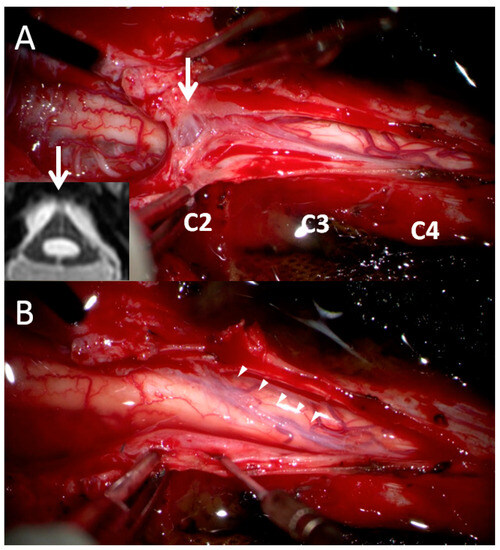

During a review of the patient’s cervical MRI series from previous years, a notable finding was made at the C2 level; that is, a thick arachnoid band was discovered to be attached to the spinal cord and the dural sac, causing the cord to take on a triangular shape in the axial view. This characteristic change in cord shape was termed the “delta cord” sign (Figure 2). Over time, progression of the syrinx from the C2 level to the C4 level was observed. After consideration of potential factors that could contribute to recurrent syringomyelia, postoperative adhesive arachnoiditis was suspected.

Figure 2.

Axial view of the C2 level at multiple time points. (A) Three months after the first surgery. (B) After 1 year, a thick arachnoid band (white arrow) had attached to the posterior aspect of the thecal sac, giving the cord a triangular shape, that is, the “delta cord” sign. Syrinx progression was observed from that point onward. (C) The spinal cord had attached to the thecal sac, and syrinx progression and cord edematous change were observed.

In order to address the postoperative adhesive arachnoiditis, a third surgery was performed. This surgery involved laminoplasty of C3–4 and extensive duroplasty from the suboccipital region to the C4 level. During the surgery, a thick arachnoid band was discovered. This band tethered the cord at the C2 level, confirming the presence of the delta cord sign. After separation of the arachnoid band, the syrinx collapsed, and the arachnoid space was no longer obstructed (Figure 3). After 1 year of postoperative follow-up, the syrinx collapsed, and an improvement of the edematous change in the spinal cord was observed (Figure 4). In addition, the patient’s functional status improved, with his mJOA score increasing from 10 to 11 and his Barthel Index score increasing from 50 to 60. Thus, he was able to walk with the assistance of a cane and perform the majority of his daily tasks, albeit with some dependency. He continued to experience residual paresthesia in his upper limbs and left lower limb.

Figure 3.

Surgical findings. (A) At the C2 level, a thick arachnoid band (white arrow) extended to the C4 level and obstructed CSF flow between the cranial and caudal sites. This finding was consistent with our previous MRI finding of the delta cord sign (we rotated the axial MRI view 180° to match the surgical finding). (B) After the release of the arachnoid band (arrow heads), the cord collapsed and connected CSF flow from the cranial and caudal sites.